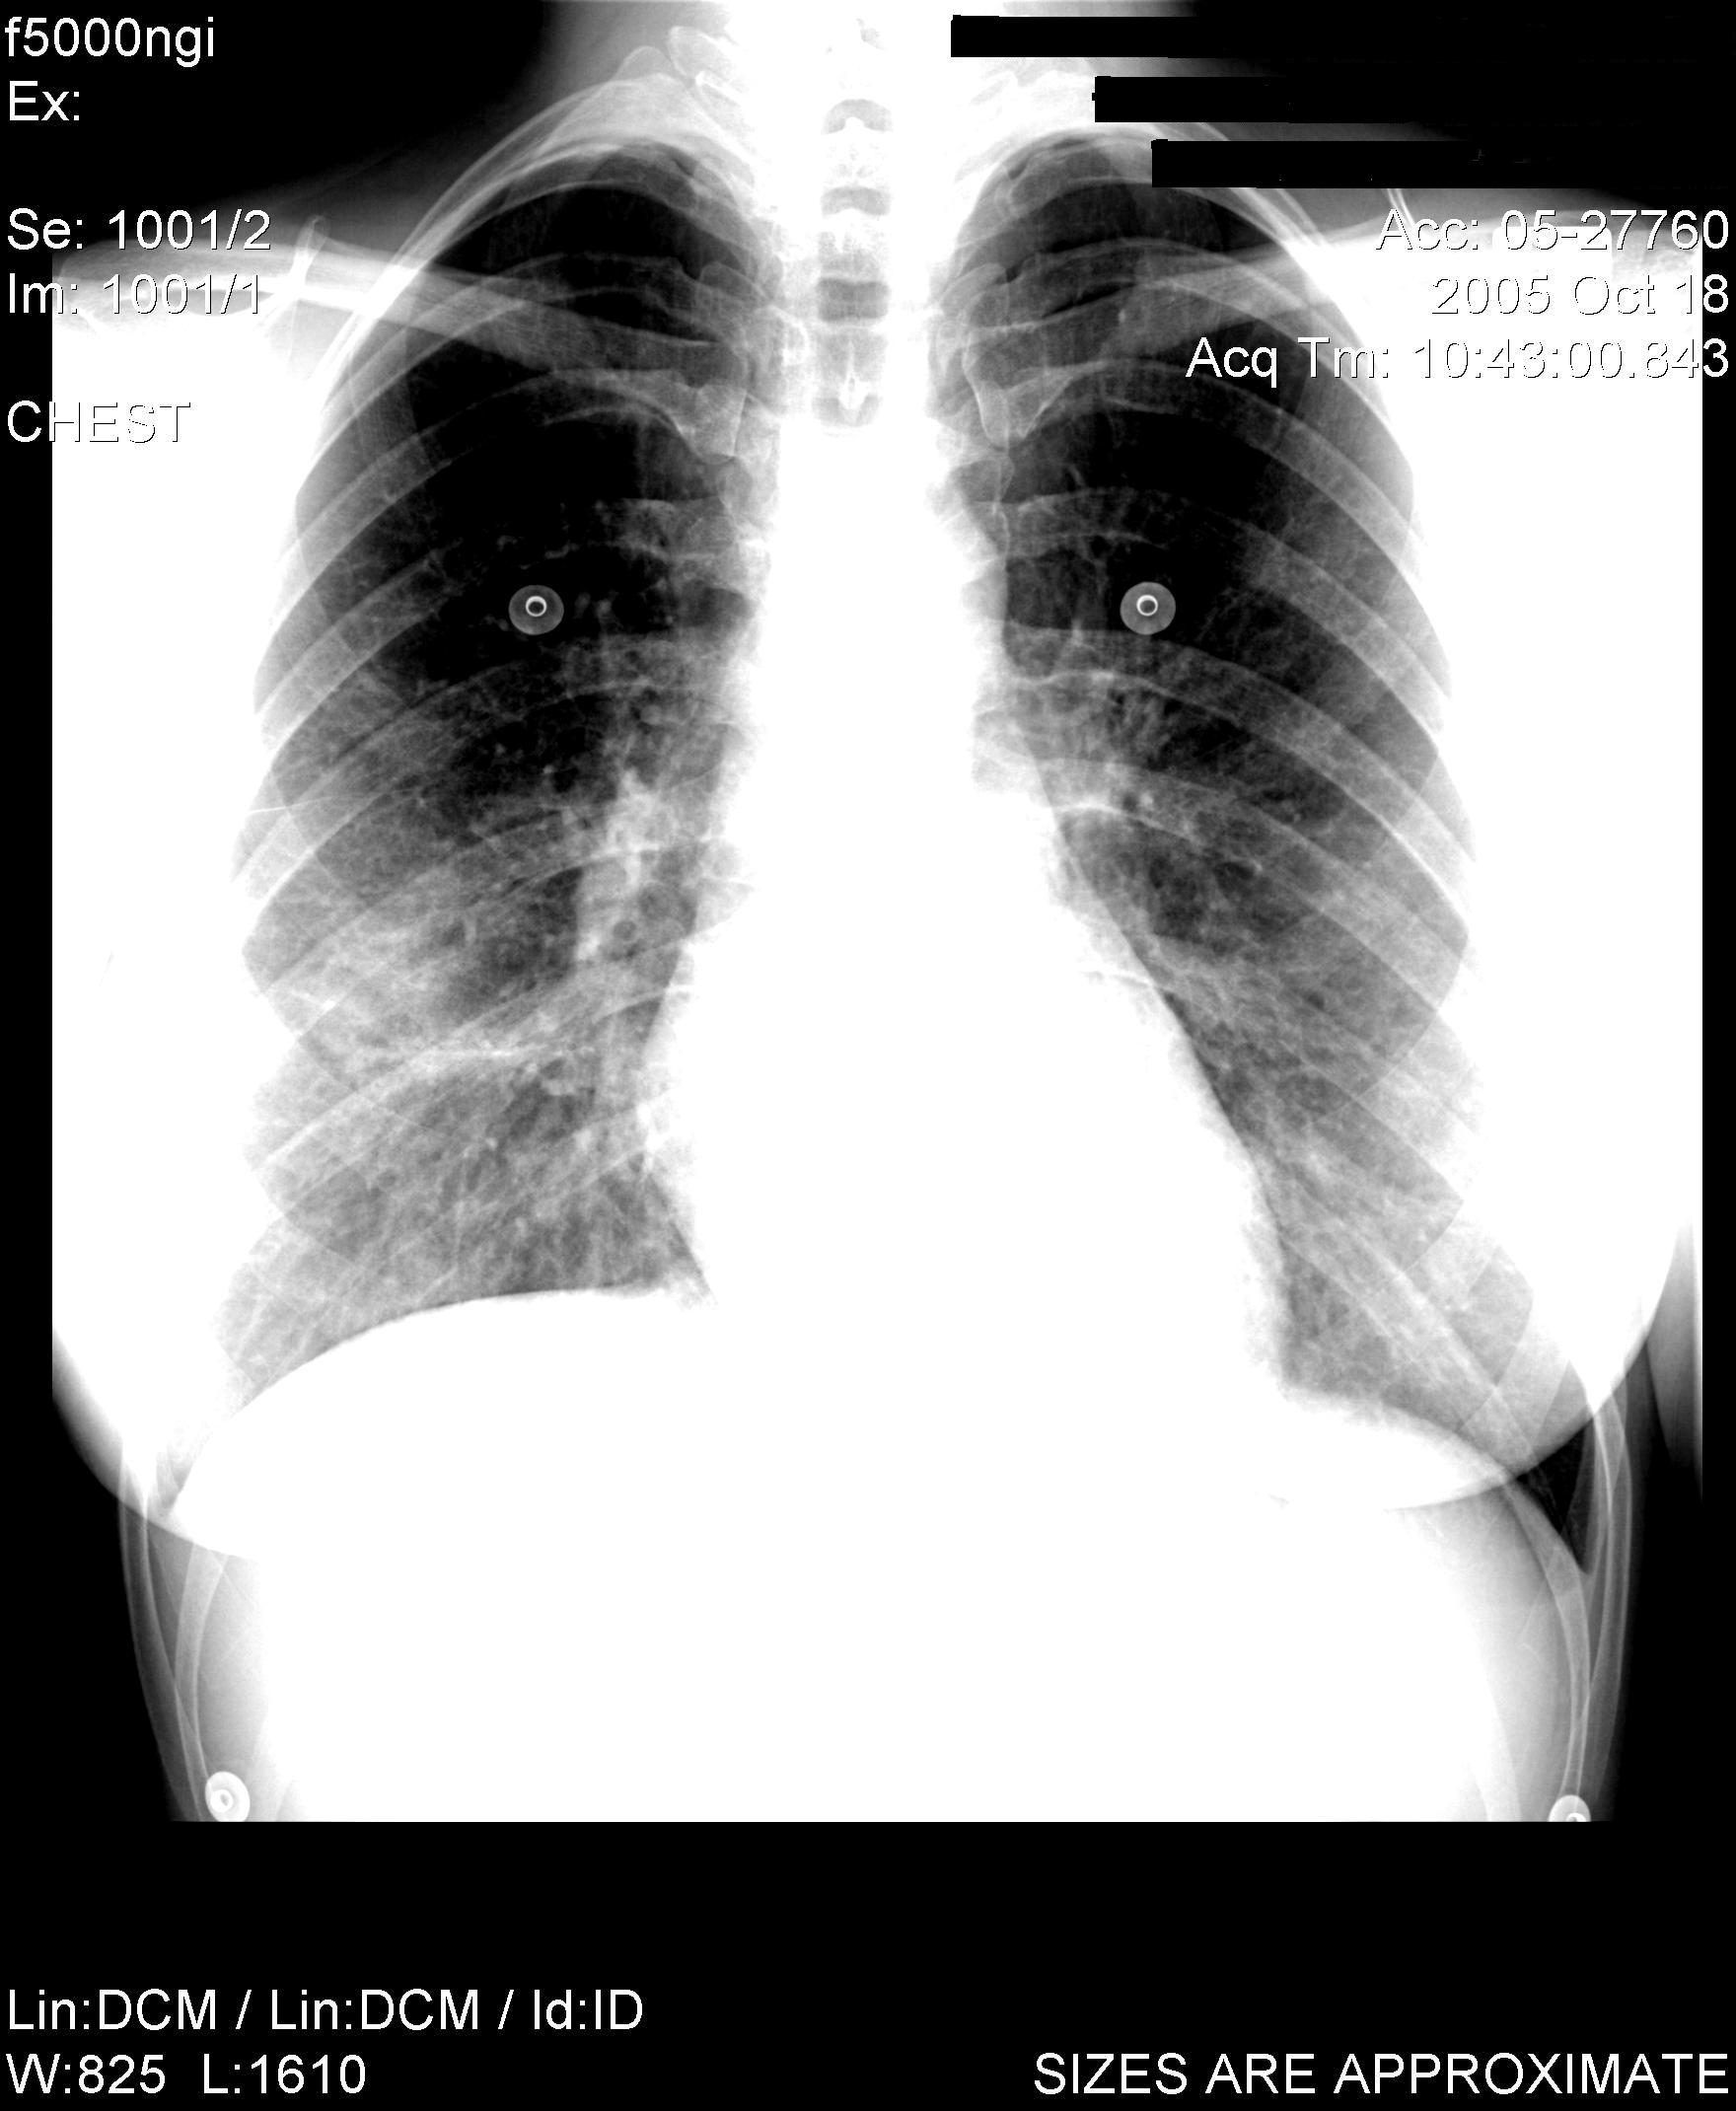

6. Three of these patients developed a nonproductive cough, dyspnea with exertion and minimal or no abnormal findings on auscultation. Chest radiographs at the time of the initial presentation showed basilar infiltrates similar to this case. Pulmonary function testing during their initial presentations showed decreased lung volumes without a primary obstructive disease. All of the patients improved with removal of exposure to further cobalt (+/- addition of systemic corticosteroids), and each recurred when they were re-introduced to environments with cobalt